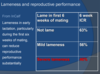

Lameness and reproductive performance?